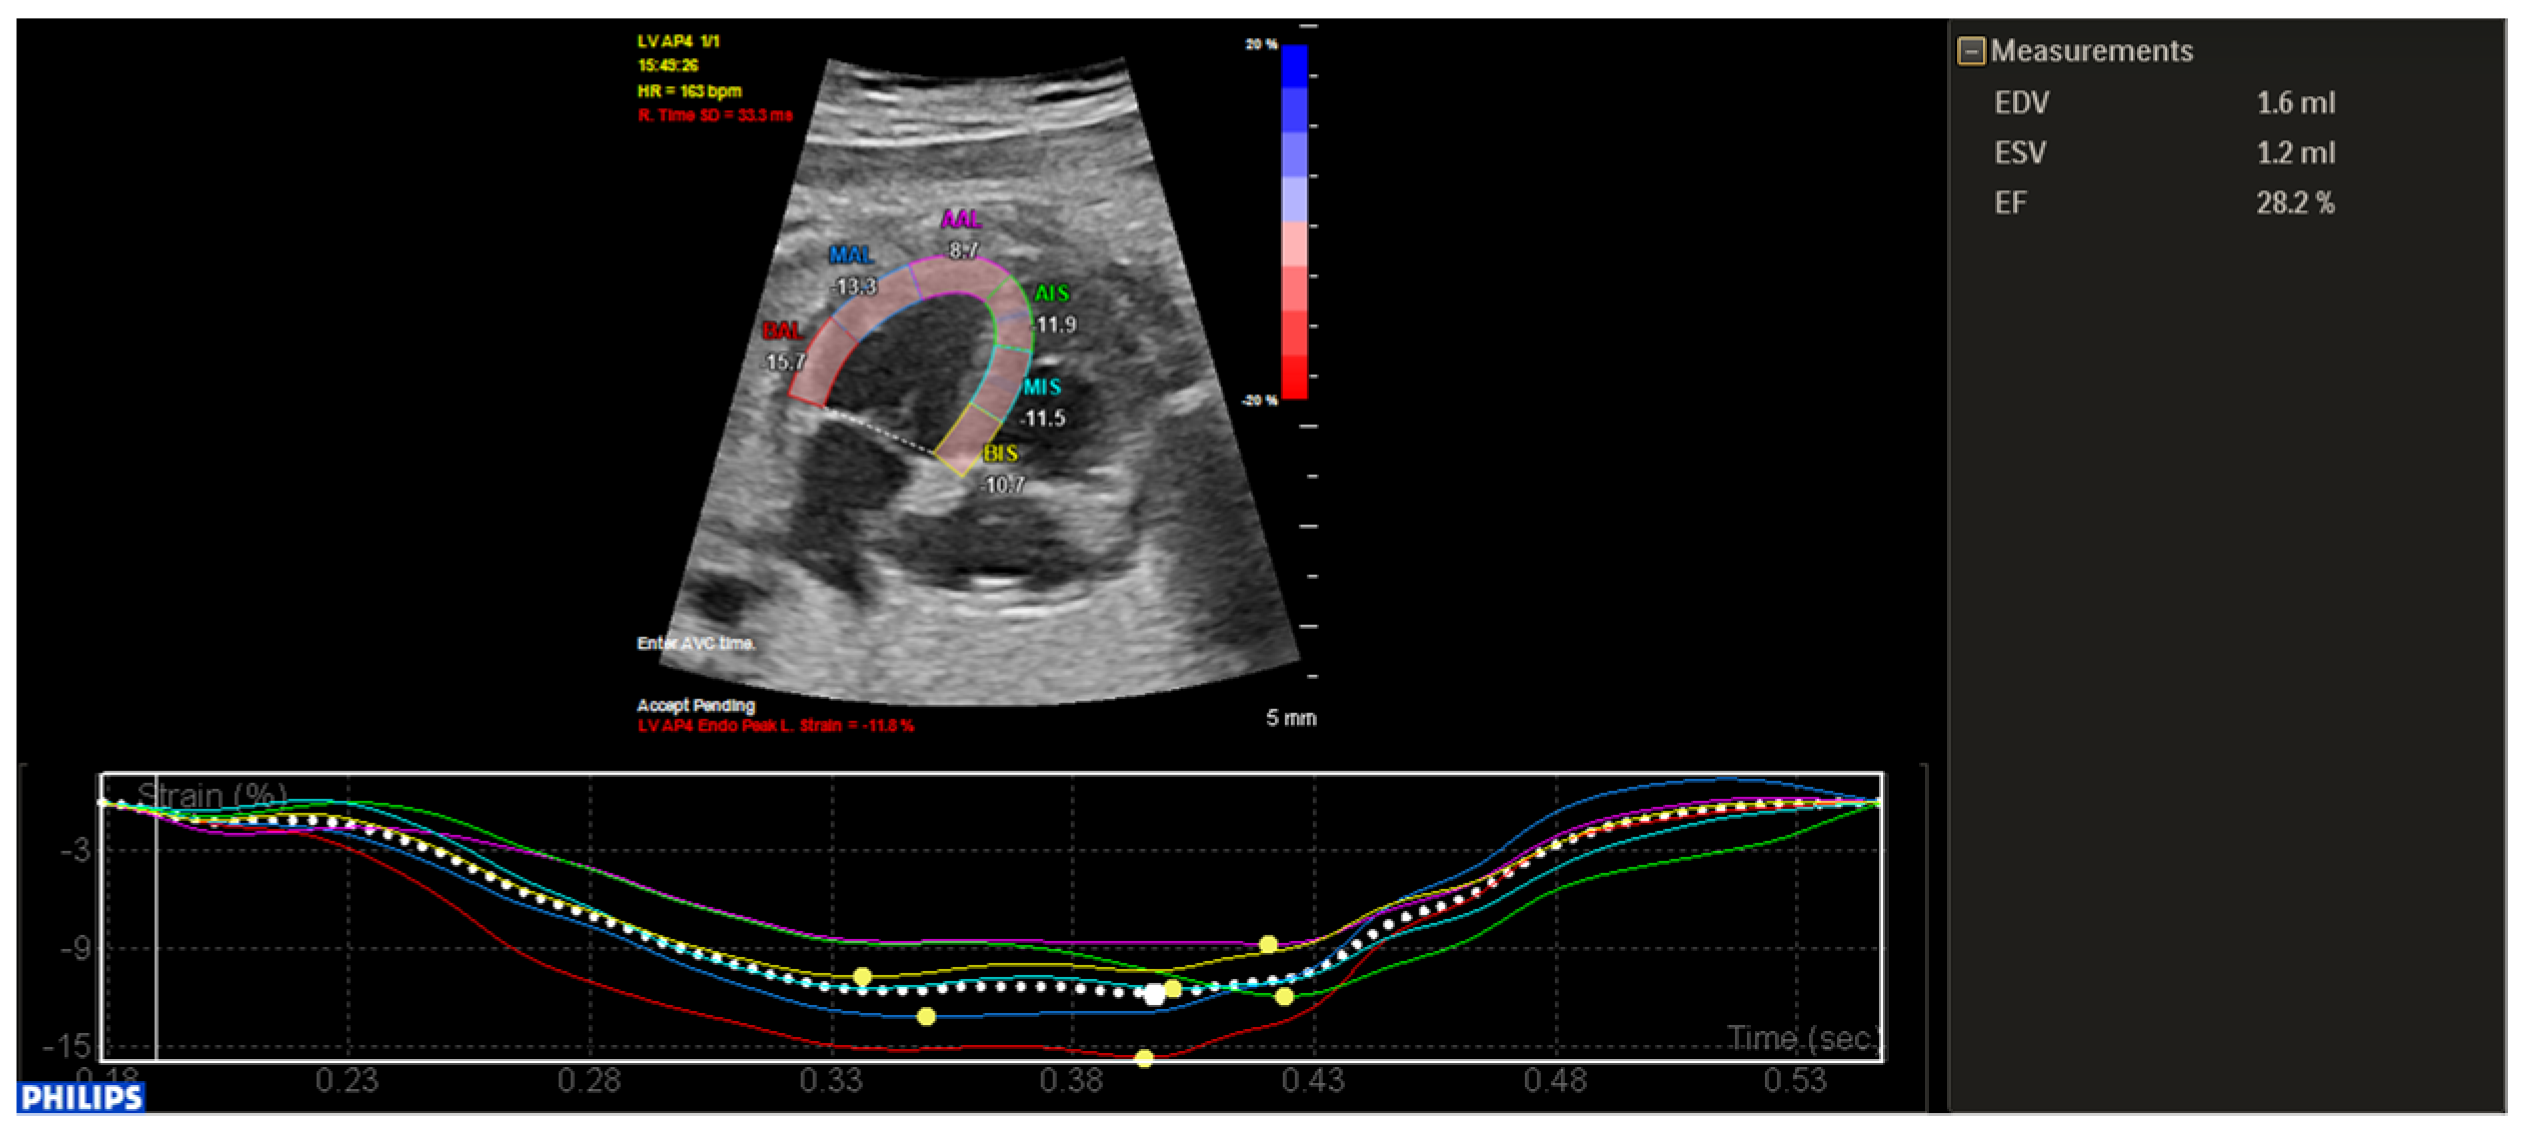

2. Case Description